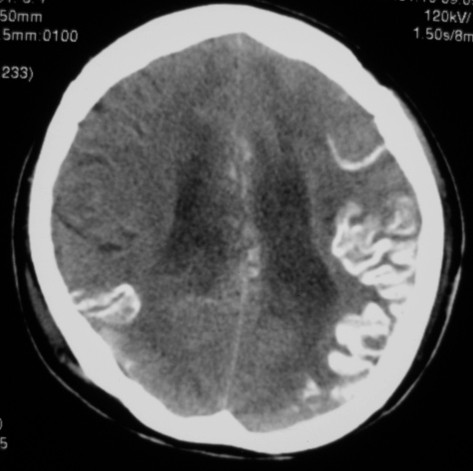

第一次ct片脑出血术后,出血吸收期。第二次ct 片左颞顶枕部及右颞顶部有脑回样高密度影。考虑珠网膜下腔出血。脑出血术后改变,脑出血恢复期 并脑积水。

是蛛网膜下腔出血么?蛛网膜下腔出血应该在脑沟里,而此高密度影是沿脑回分布,应该是脑膜感染后钙化灶形成。

应该是脑回钙化,不是出血

脑回状高密度影,首先要考虑脑颜面血管瘤病,不知高密度区ct值多少,对于鉴别是蛛网膜下腔出血还是钙化有意义,只是病人半月前“钙化”还较局限,因此还是考虑与脑出血有关。当然要密切结合病史及临床,增强扫描有意义。

考虑是脑回钙化,不是出血,什末样的蛛网膜下腔出血是这样的?我没见过!考虑脑炎性钙化,要结合病史!